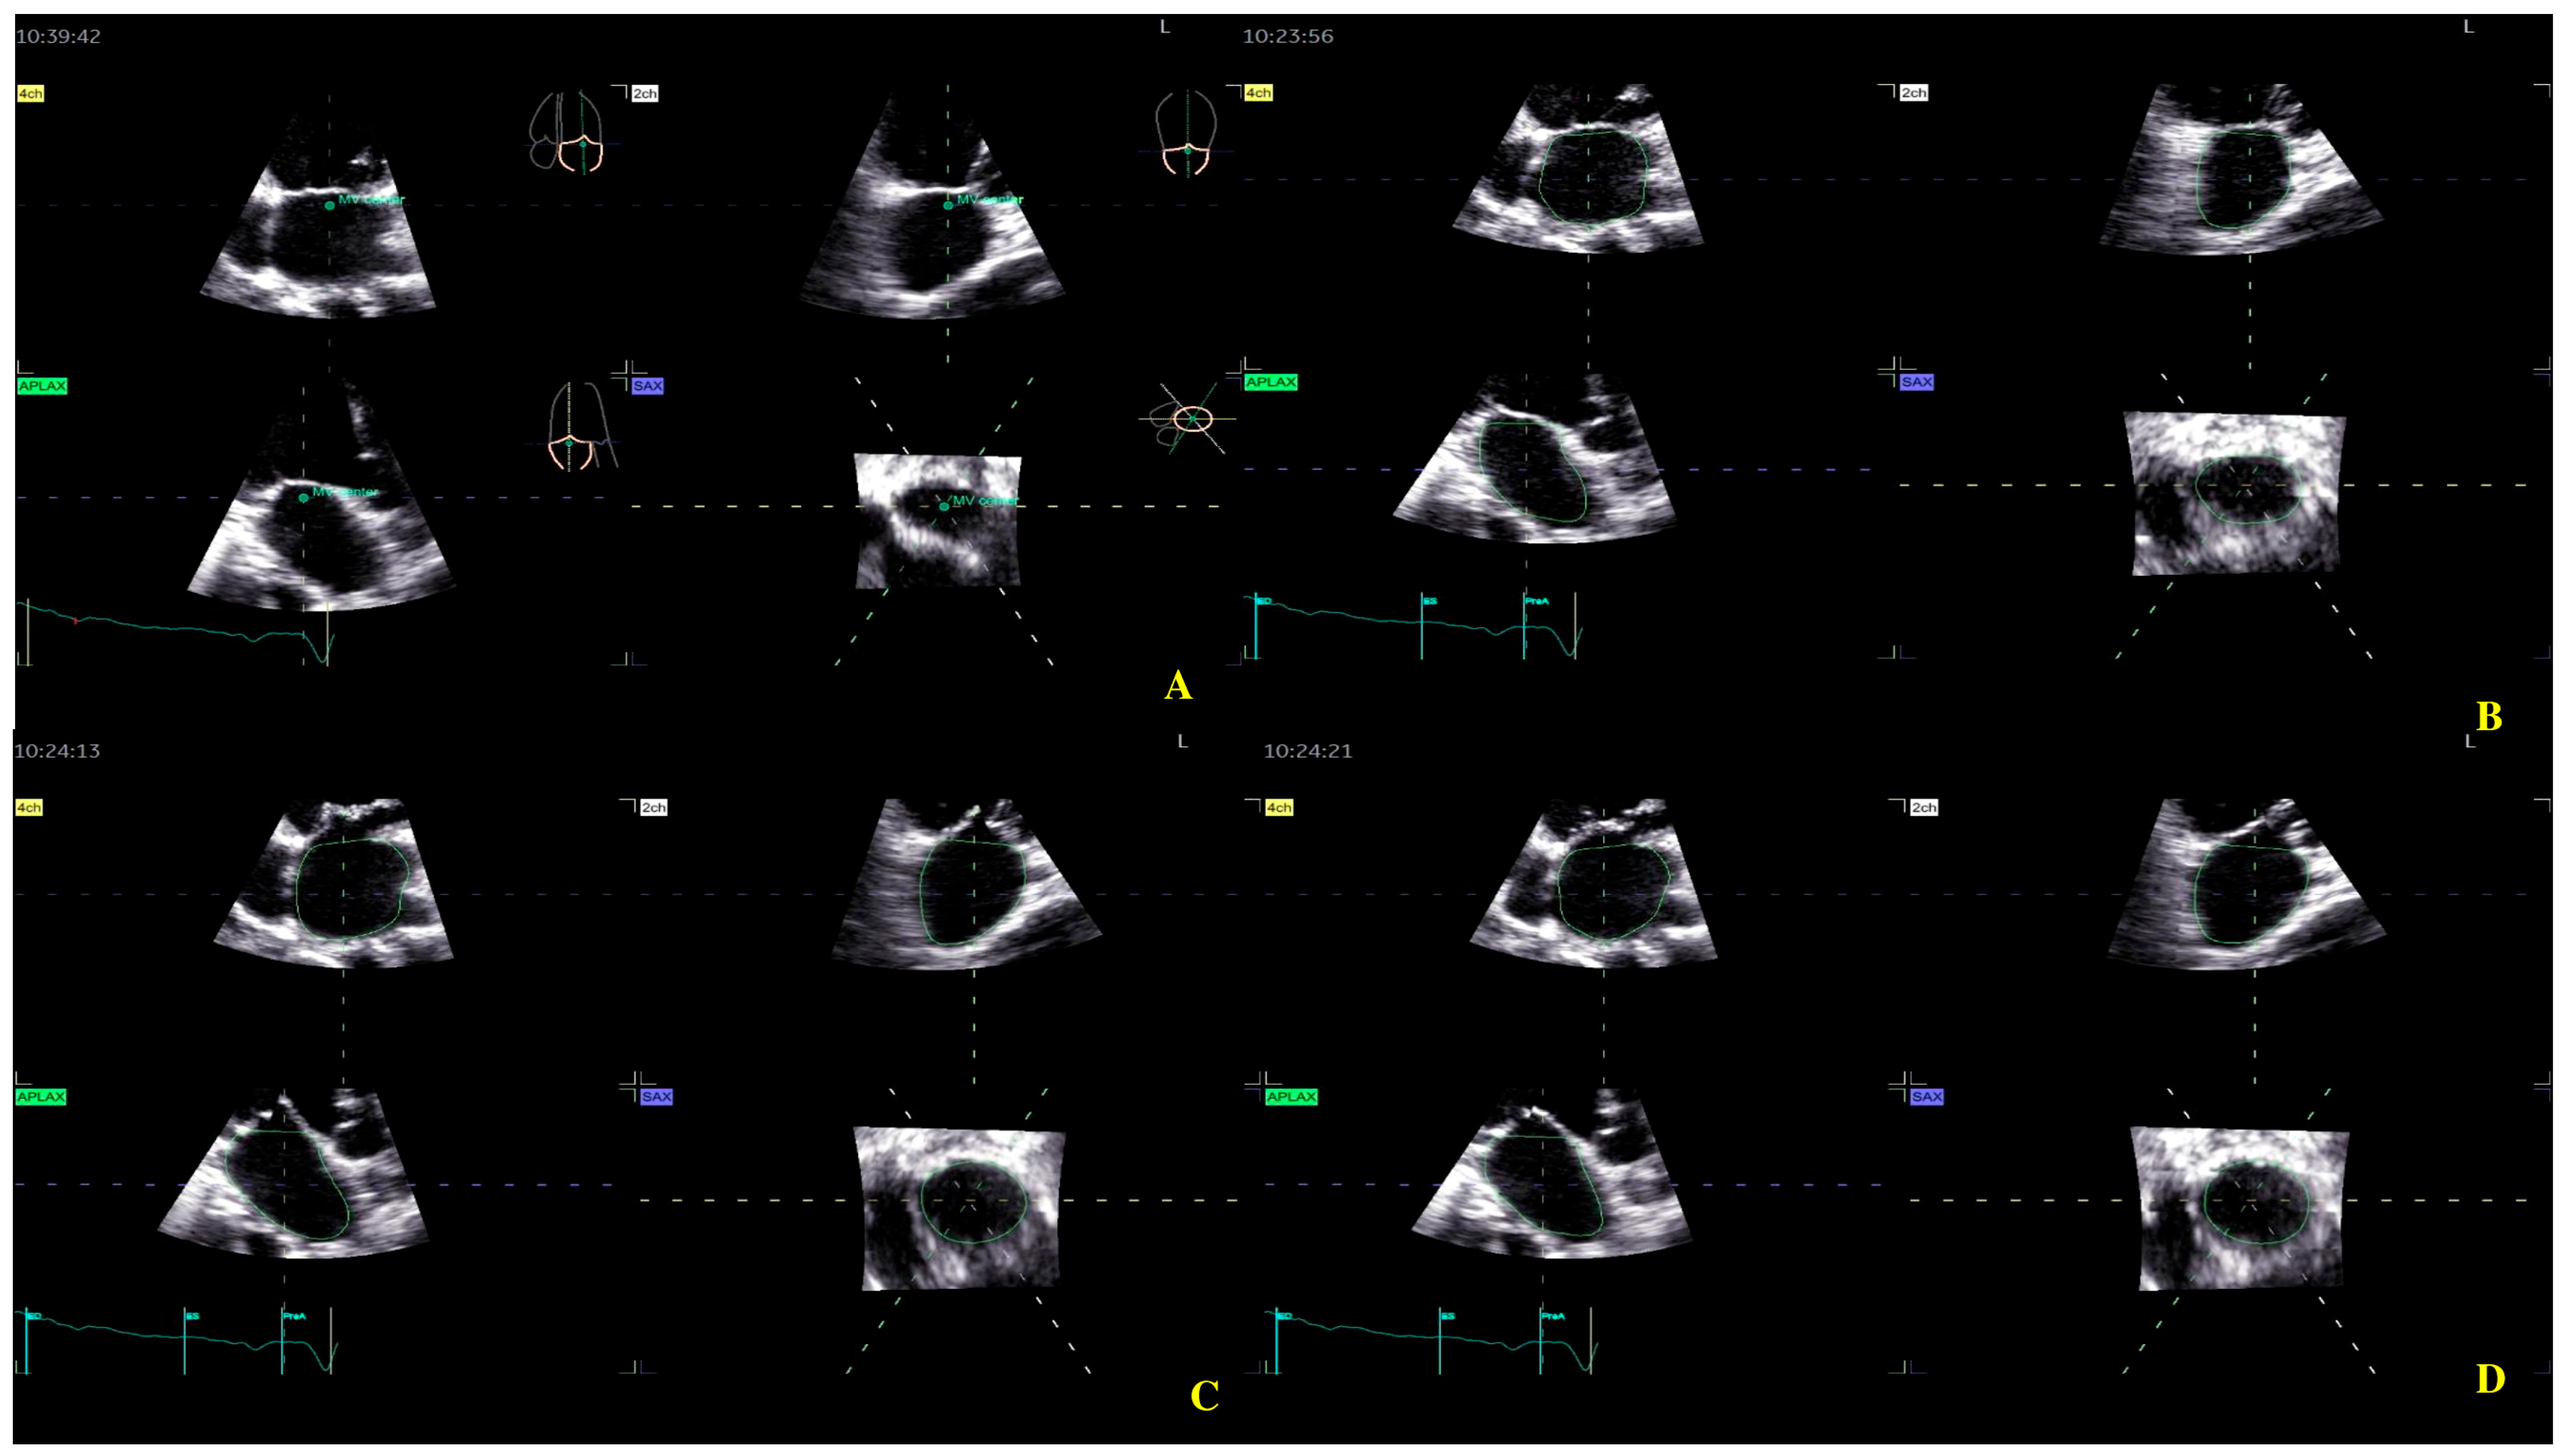

For the LA quantification, the landmark was located in the center of the MV at the annulus level in the three planes (Figure 2). The segmentation algorithm computes the deformation of the model. For LAS longitudinal and circumferential strain evaluation, the ‘review’ function was selected. The software automatically detected the endocardial border in three-dimensional space throughout the cardiac cycle. Care was taken to ensure correct delineation by rotating along the long axis of the LA. The investigator manually adjusted the border at end-diastole (Figure 2A), end-systole (Figure 2B), and pre-atrial contraction (Figure 2C) to include the entire atrium and exclude the pulmonary veins and LA appendage. The software automatically generated all left atrium parameters, including the LAS (Figure 3) [19].

Figure 2.

Left atrium segmentation: (A) MV center identification; (B) left atrium endocardial border in three-dimensional spaces during diastole; (C) left atrium endocardial border in three-dimensional spaces during systole; (D) left atrium endocardial border in three-dimensional spaces before atrial contraction.